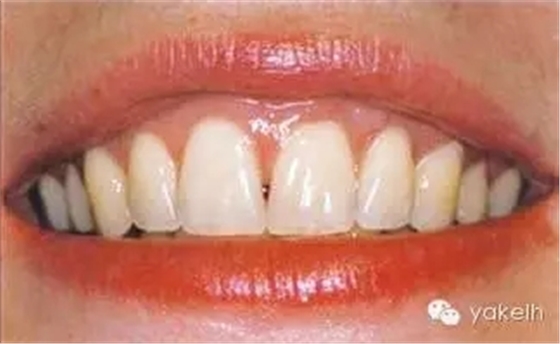

圖5.11 (a)患者休息放松狀態(tài)下的嘴唇——上下唇不能完全閉合。(b)右上尖牙和側(cè)切牙呈Ⅰ類牙齦退縮。(c)左上頜尖牙和側(cè)切牙呈Ⅱ類牙齦退縮。(d)先用圓形眼科刀片開始做溝內(nèi)切口。(e)使用探針在袋內(nèi)垂直探查貫通隧道,越過膜齦聯(lián)合。(f)使用探針在隧道內(nèi)橫向探查貫通,保留齦乳頭尖端附著于骨面。(g)從腭部取結締組織移植物,使用絲線牽引,將厚度和大小足夠的結締組織瓣插入隧道內(nèi)。(h)通過懸吊縫合將組織瓣冠向復位,穩(wěn)定結締組織瓣。(i)術后6個月,上頜右側(cè)觀。(j)上頜左側(cè)觀,可見牙齦厚度以及色澤的協(xié)調(diào)性均得到改善。(k)術后6個月正面觀,牙敏感癥狀消失。(l)術后1年的全口影像,顯示雙側(cè)的牙齦退縮均被完全覆蓋,牙齦邊緣增厚且穩(wěn)定,與釉牙骨質(zhì)界輪廓一致,也與左側(cè)中切牙釉質(zhì)缺損輪廓一致。(m)患者嶄新的笑容,可見側(cè)切牙及尖牙的齦緣無退縮。